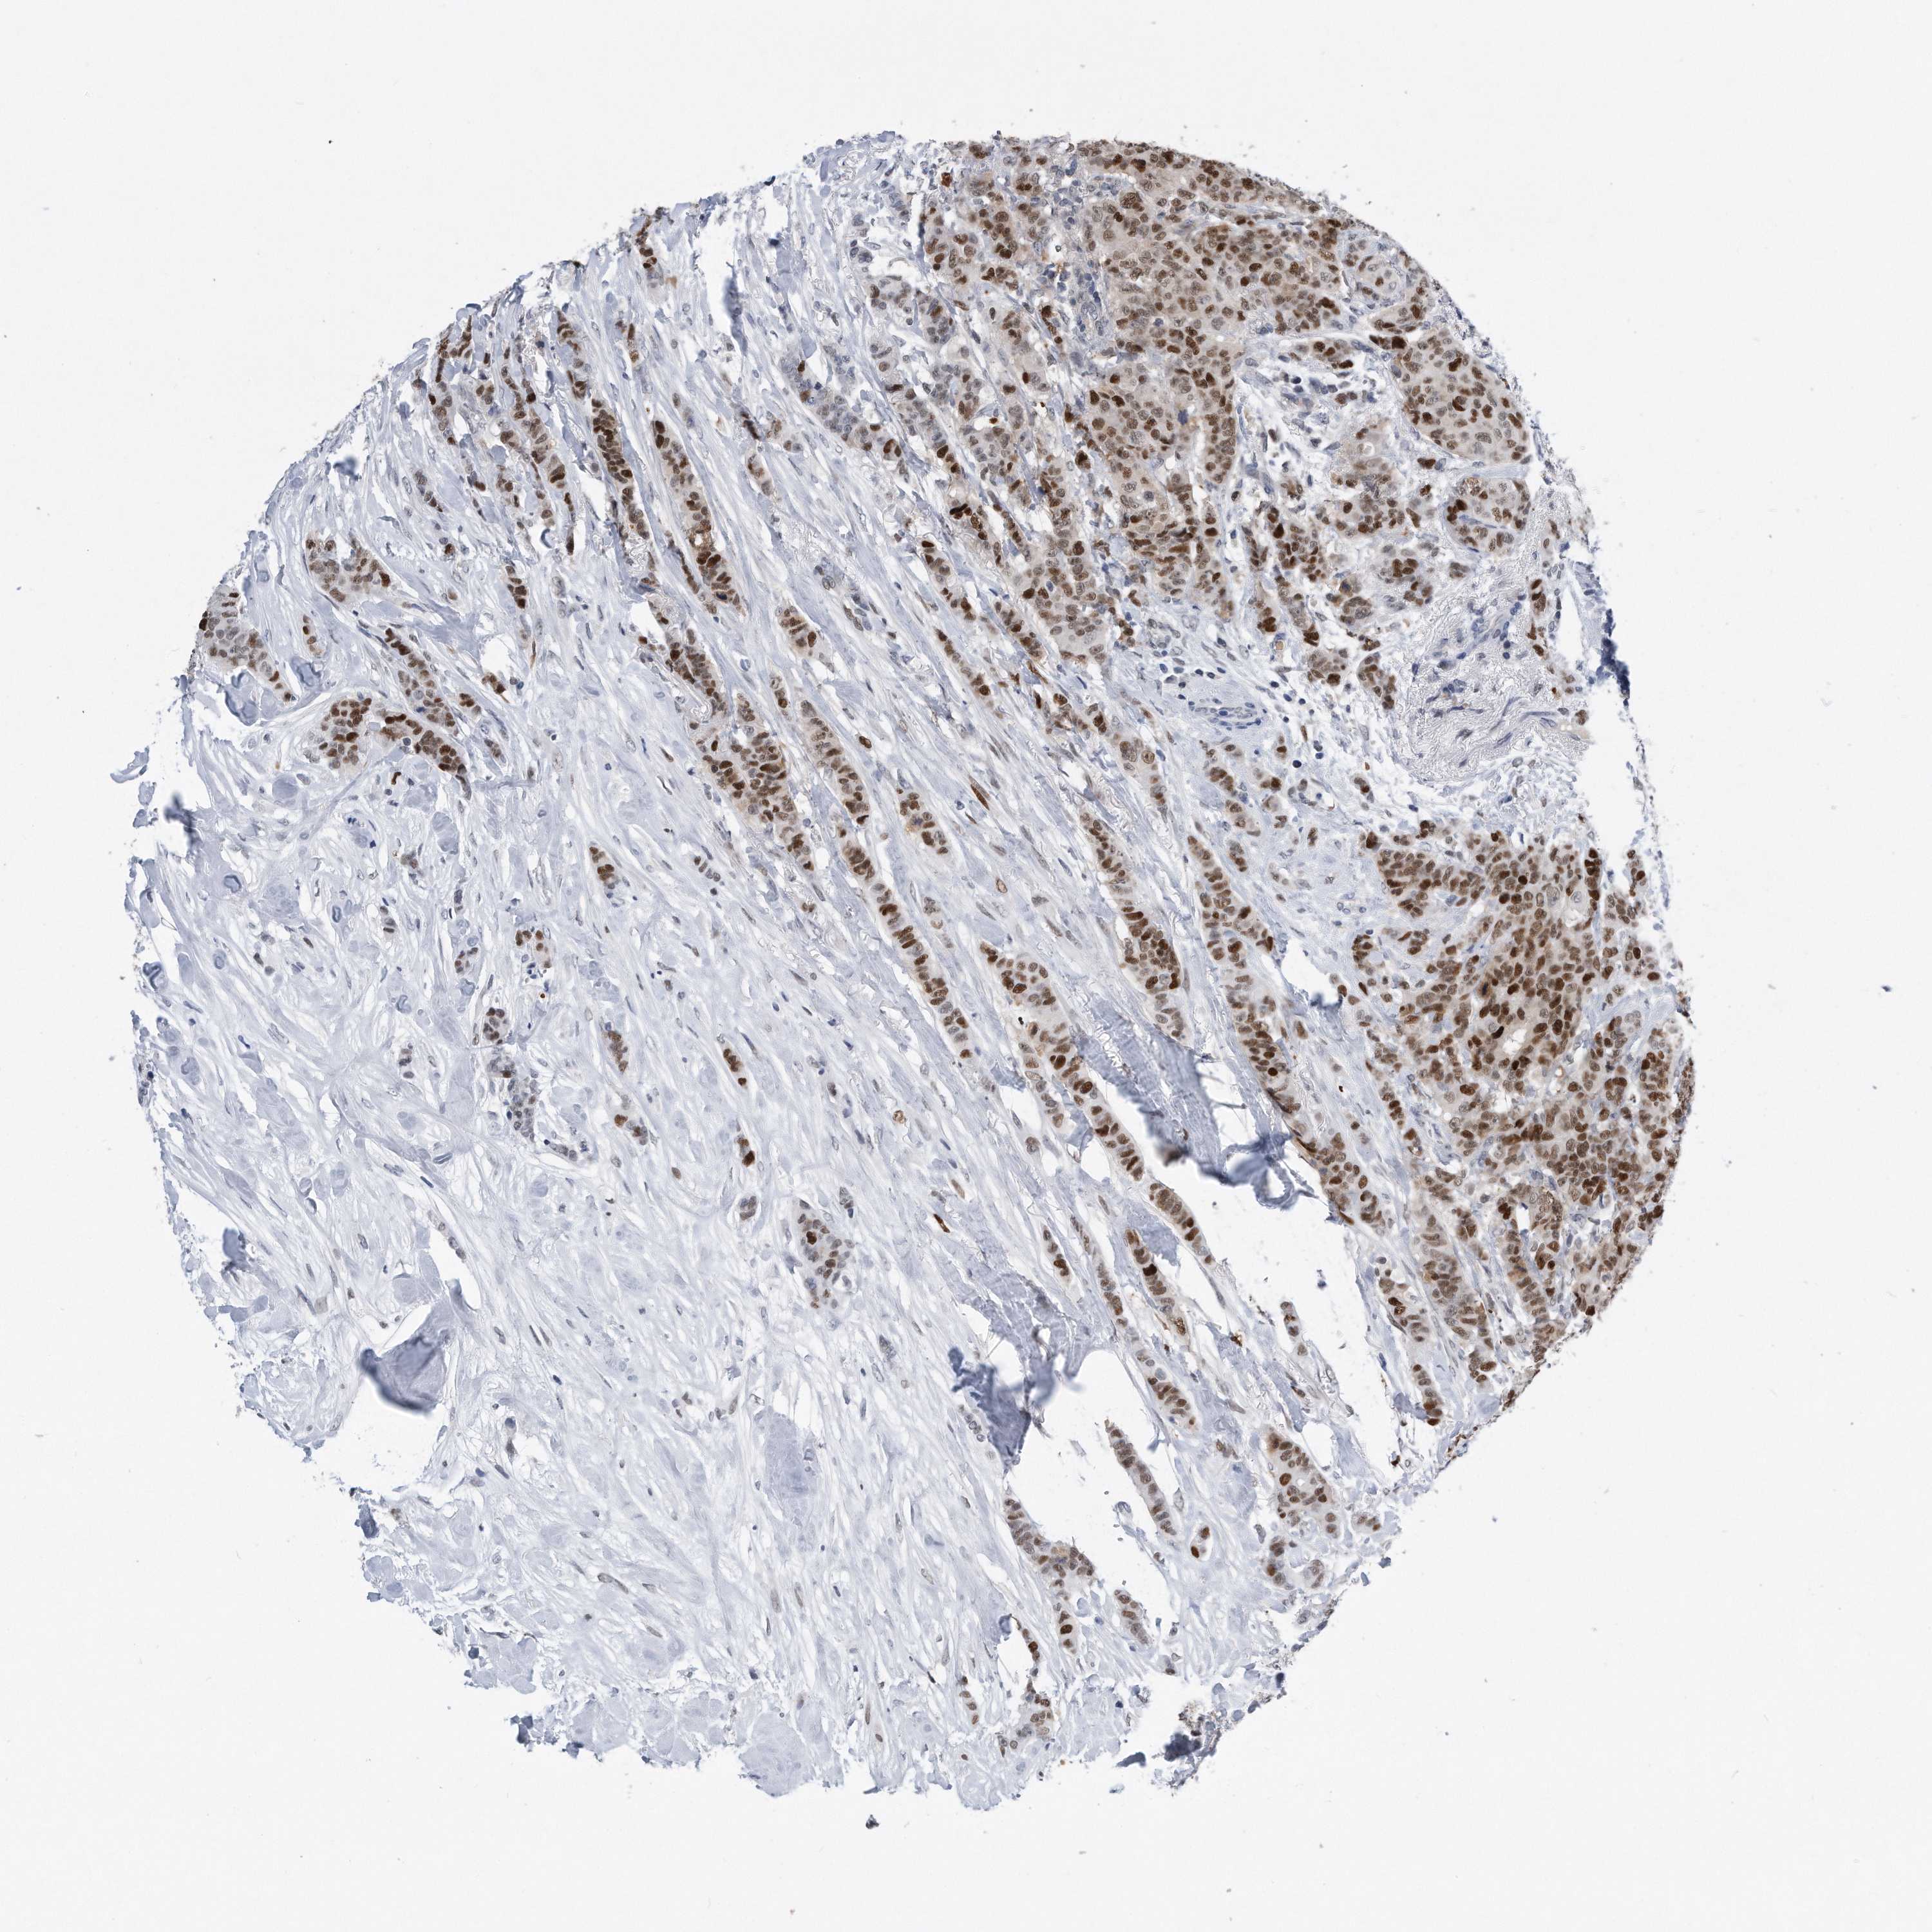

CANCER BREAST CANCER Show tissue menu

BRCA TCGA BRCA VALIDATION PROTEIN EXPRESSION

Breast cancer

Human cancer